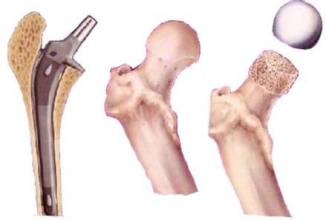

导读: 股骨头坏死了可以吃哪些蔬菜?股骨头坏死是较常见的一种骨关节疾病,治疗需要一定的时间。在治疗过程中,患者的合理饮食能起到很重要的作用,尤其是新鲜蔬菜,能补充人体营养,帮助身体康复。那么,股骨头坏死了可以

导读: 从哪些方面预防股骨头坏死?一种疾病的发病因素一般都是比较多的,能从许多方面来诱发疾病。因此要预防疾病,也要从多方面入手,比如股骨头坏死。这是一种较常见的骨病,影响大,要避免股骨头坏死危害自身健康安全,

导读: 股骨头坏死在天气变化时如何保护自己?生活中,很多人都会受到股骨头坏死的困扰。此病属于慢性隐性疾病,其病变过程复杂而漫长,而且容易受到天气变化的影响。天气对股骨头坏死的影响主要体现在寒冷和潮湿这两种天气

导读: 生活中如何调理股骨头坏死?股骨头坏死是一种很常见的疾病,患上股骨头坏死对我们简直就是一种噩梦,那么现实生活中我们又如何在家调理呢?又该怎样调理呢?下面由我院骨科专家为大家推荐一种有效的家中调理的按摩办

导读: 如果说大家平时的饮食不规律的话,那么我们可能患上很多的疾病的,既然饮食可以引起很多的疾病的发生,那么饮食自然也是可以有效控制疾病的病情的发展,而针对股骨头坏死也是这样的。在平时可以注意一下自己的饮食,